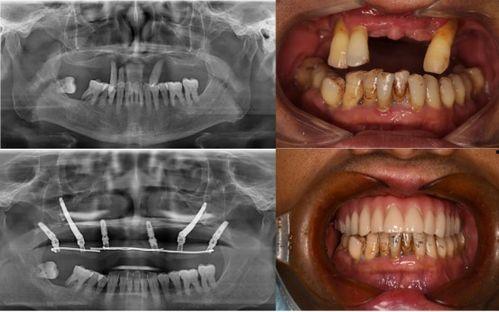

首先,让我们来回顾一下这个事件。据网友爆料,佛山某口腔医院在进行种植牙手术时,竟然出现了严重的医疗事故。视频中,一位患者在手术过程中突然大出血,医护人员却显得手忙脚乱,场面一度十分混乱。这个视频一经曝光,立刻引起了广大网友的关注和热议。

那么,这个医疗事故背后到底隐藏着什么真相呢?据知情人士透露,这家口腔医院在手术过程中存在诸多违规操作。首先,手术医生并未具备相应的资质,而是由一位实习医生主刀。其次,手术过程中使用的医疗器械也存在严重问题,比如消毒不彻底、过期等。这些因素共同导致了这场悲剧的发生。

面对这场突如其来的灾难,患者们的心情无疑是悲痛的。他们纷纷表示,自己原本希望通过种植牙手术重拾自信,却没想到遭遇了这样的噩梦。为了维权,患者们开始四处奔波,寻求法律援助。维权之路并非一帆风顺,他们面临着诸多困难。